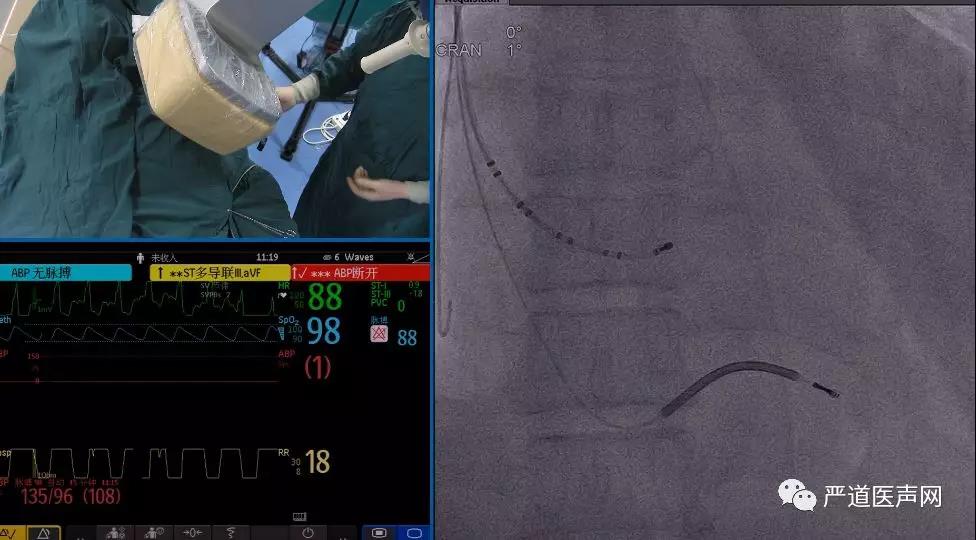

电生理十级寻找冠状窦,外鞘沿电生理十级进入冠状静脉。

术中使用造影球囊显示冠状静脉分支,选择粗大侧静脉为靶静脉。

选择Sprial L导线,通过PTCA导丝将导线送入侧静脉远端,贴靠稳定。